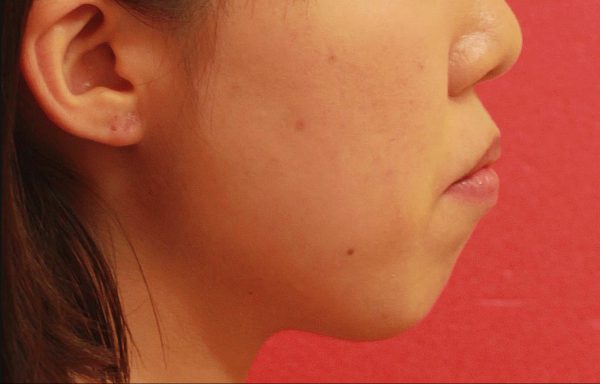

14歳 女性 「 口が 閉じにくい 」 ( 上下顎前突症 )

14歳の 女性です。

”出っ歯” と口もとを治したいとの事で来院されました。

前歯の重なりが気になります。

上の前歯が 傾斜しているため

口もとが 大きく出っ張っています。

お母さんとご本人で来院されたのですが、

お母さんが 娘さんの「もっさりとした」口もとを気にされていました。

このため、お口が 閉じにくいそうです。

また、口元が出っ張っているため 口角が上がらず 不機嫌そうな口もとに見えてしまいます。

叢生を伴う 上下顎前突症 です

口もとの 出っ張り感と 前歯のねじれを治したい

との事で上下左右の抜歯を行い 前歯を後方に移動させ口もとを下げました。

2018年の3月30日にスタートして 2019年の10月15日に 終 了 しました。

治療期間は 19か月でした

前歯の”出っ歯”と重なり は解消され、前歯は 大きく下がりました。

口もと の出っ張り感は 解消されました

口もとの 印象が 大きく変わりました

素敵な笑顔になりました! (#^.^#)

14歳 女性 叢生を伴う 上下顎前突症 治療期間18か月 唇側矯正装置(ホワイトワイヤー)を使用した上下顎第一小臼歯抜歯治療 参考治療費 約65万円 (精密検査から終了まで) 矯正治療に伴う副作用の歯肉退縮、知覚過敏、失活、歯根吸収などは認められませんでした。